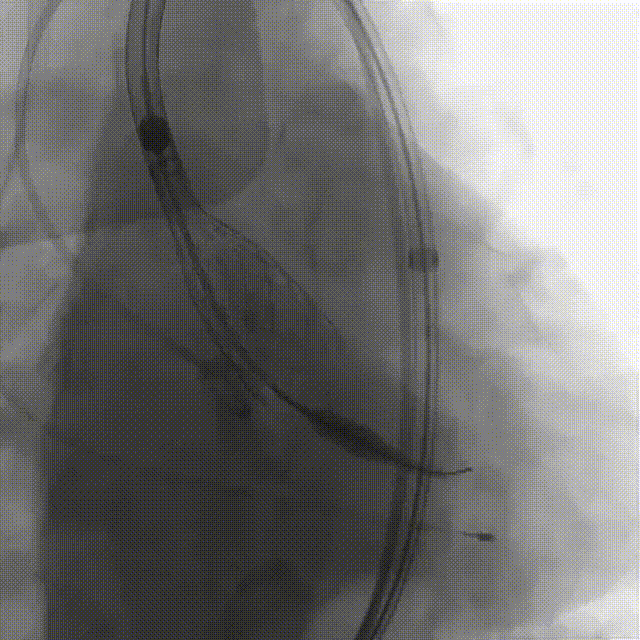

刘煜昊教授 阜外华中心血管病医院(点击查看专家详细简历) 首瓣选耐久,干瓣护航全生命周期管理 2025年ESC专家共识里指出:“推荐第一个瓣膜要选经证实具有长期耐用性的外科瓣膜与经导管瓣膜,以降低再次介入治疗的可能性 ,对于瓣环较小、根据预测有效瓣口面积(EOA)评估存在严重 PPM 风险的患者,可采用主动脉根部扩大术联合 SAVR,或植入环上瓣,对于小瓣环患者自展瓣拥有比较好的血流动力学优势”。 每一次术前评估,都是我们与患者携手面对未知的起点。我们始终以患者全生命周期获益为核心,在瓣膜选择与术式规划中,不只着眼于当下解剖适配,综合评估解剖条件、预期寿命与生活质量。从年轻患者到高龄人群,瓣膜耐久性与血流动力学稳定性始终是决策核心! 陈同峰教授 阜外华中心血管病医院(点击查看专家详细简历) 医学的进步正不断拓宽生命的边界,每一次术前评估都是对生命尊严的深度凝视,技术与人文的交融,让风险不再仅是数字的堆叠,而是成为医者与患者共同面对未知的勇气见证。术中瓣膜释放结束,到了导管测压的时候,我惊喜:瓣膜不错啊,压差为0,这不仅仅得益于瓣膜形态的设计,更是环上瓣及瓣叶材质优质的体现,感受到了 Prostyle A瓣膜在血流动力学上的卓越表现,其采用的抗钙化处理技术有效延长了瓣膜的耐久性,为患者长期生存提供了更可靠的保障。 患者病史 主诉:心慌半月; 门急诊诊断:心悸,冠状动脉粥样硬化性心脏病,心脏瓣膜病,主动脉瓣狭窄,高血压,甲状腺术后; 现病史:半月前无明显诱因出现心慌,呈间断性,伴心悸、出汗,伴头晕,无咳嗽、咳痰,无恶心、呕吐,无双下肢水肿,无放射痛及意识障碍,休息约几分钟后可自行缓解,症状反复发作,遂来我院就诊。 术前超声提示:室间隔增厚;主动脉瓣退行性变并重度狭窄;升主动脉明显增宽;室间隔增厚。 术前CT 三叶瓣,轻度钙化集中在无窦和左窦瓣叶边缘,主动脉根部直径19.3mm,LVOT直径17.7mm,LVOT向下收窄; 窦部正常,VTC空间足够,冠脉风险低; 左室腔小,收缩末径20-25mm,“自杀左室”,循环崩溃风险高;主动脉瓣环水平夹角71.1°,横位心,过弓和跨瓣存在一定困难,备snare。 外周双侧入路内径可,双侧入路能够支持20F大鞘通过,右股低分叉。 手术策略 推荐右侧股动脉为主入路,左侧为辅助入路,右股分叉上方1cm穿刺;推荐选择AV23瓣膜,18mm球囊预扩,左右重叠位:LAO 7° CAU 35°;左冠切线位:LAO 27° CRA 16°;右窦居中位:LAO 18° CAU 9°;备Snare,建议ECMO/CPB湿备,术前术中积极补液,警惕循环崩溃风险。 手术过程 在右股动脉穿刺建立通路后,顺利送入大鞘,经食道超声及血管造影确认路径稳定。18mm球囊预扩过程中,患者血压一度下降,迅速完成扩张并立即植入AV23 ProStyle A®瓣膜。瓣膜精准释放于目标位置,超声显示无明显反流及瓣周漏,血流动力学即刻改善。 主动脉根部造影 18mm球囊预扩少量反流 输送系统柔顺跨瓣 精准定位 平稳释放 80%工作位观索位置合适 释放后导管测压,压差由术前53mmHg降为0mmHg 最终造影瓣膜位置形态良好,冠脉灌注良好,无明显瓣周漏 ProStyle A®预装干瓣——助力临床最优化解决方案: 轻松过弓,精准可控:该病例为横位心,在未使用snare的情况下,过弓和跨瓣柔顺,较细的尺寸+柔顺的输送系统通过性能得到了很好的验证; 平衡的收腰设计:该病例瓣环较小且左室腔小,AV23瓣膜的平衡收腰设计既确保了锚定安全性,又保证了EOA,有效降低了循环崩溃风险,而术后0mmHg的压差的表现更加证明了优秀的血流动力学,提高了瓣膜的耐久性; 预装干瓣 便捷顺安:金仕生物专利抗钙化技术运用纳米技术去除组织内的细胞碎片和磷脂,封闭游离醛基,从根本上阻断了瓣膜钙化的多项因素,显著提升了瓣膜的耐久性;同时,相比较传统戊二醛保存方式,干式存储最大限度的保留心包的亲水亲油平衡,还原组织天然曲柔性,进一步保障了瓣叶开合,保证长期耐久性。 专家简介 王小虎 阜外华中心血管病医院(点击查看专家详细简历) 陈冲 阜外华中心血管病医院(点击查看专家详细简历) 赵一品 阜外华中心血管病医院(点击查看专家详细简历)